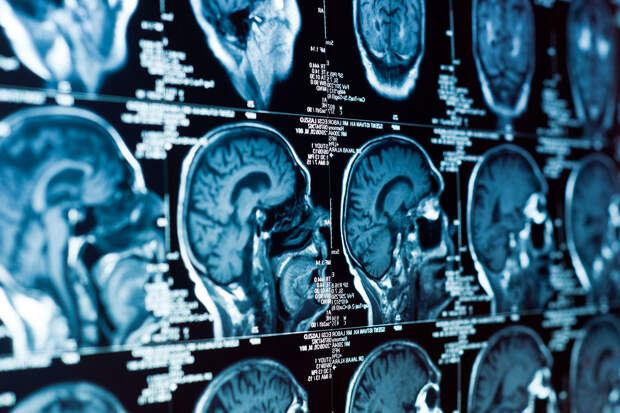

Молекулы, вырабатываемые в астроцитах — вспомогательных клетках мозга, — могут способствовать развитию деменции. К такому выводу пришли ученые из Медицинского центра Вейла Корнелла. Работа опубликована в журнале Nature Metabolism.